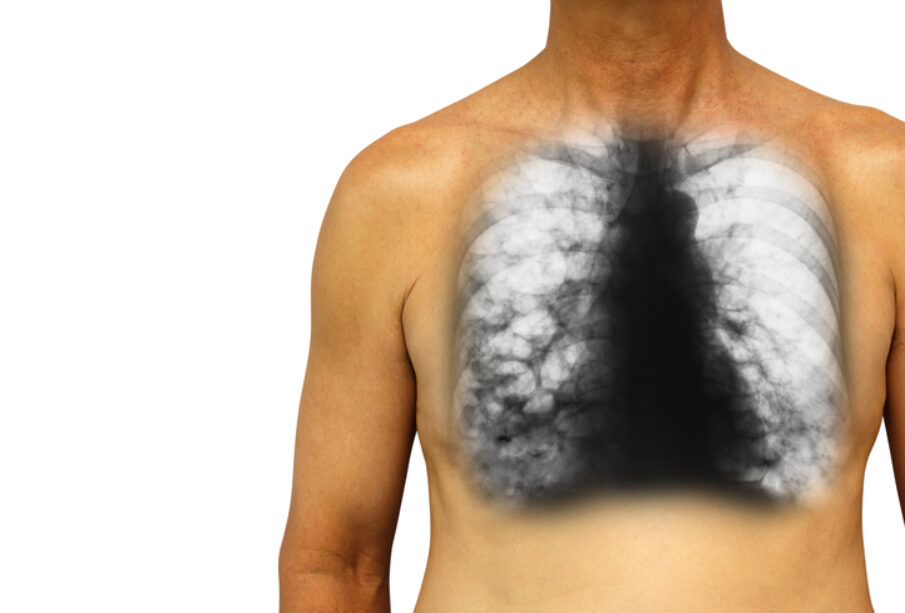

Περίπου το 80% των ατόμων με το συγκεκριμένο σύνδρομο αναπτύσσουν κύστεις στους πνεύμονες. Τις περισσότερες φορές, οι κύστεις αυτές δεν προκαλούν δυσάρεστα συμπτώματα και δεν επηρεάζουν τη λειτουργία των πνευμόνων.

Έως και το ένα τρίτο των ασθενών μπορεί να παρουσιάσει υποτροπιάζοντα προβλήματα στους πνεύμονες, όπως είναι ο πνευμοθώρακας. Επιπλέον, το 15% έως 30% των πασχόντων ενδέχεται να αναπτύξουν όγκους στα νεφρά σε μεγαλύτερη ηλικία. Οι όγκοι αυτοί έχουν αργή εξέλιξη και εντοπίζονται πιο συχνά σε άτομα ηλικίας 48 έως 50 ετών. Για την έγκαιρη ανίχνευση των όγκων και την αποτελεσματικότερη αντιμετώπιση, συνιστώνται τακτικές απεικονιστικές εξετάσεις με αξονική τομογραφία κοιλίας.